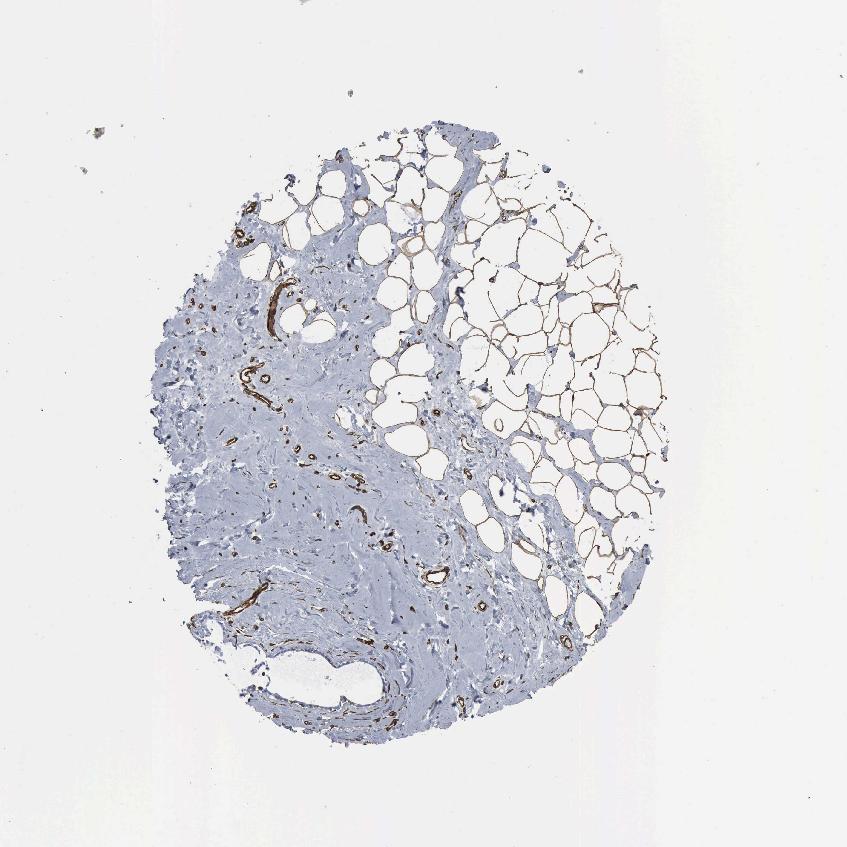

BREAST - Antibody stainingi

Antibody staining in the annotated cell types in the current human tissue is reported as not detected, low, medium, or high, based on conventional immunohistochemistry profiling in selected tissues. This score is based on the combination of the staining intensity and fraction of stained cells.

Each image is clickable and will lead to virtual microscopy that enables deeper exploration of all samples and also displays staining intensity scores, fraction scores and subcellular localization as well as patient and tissue information for each sample.

Antibody HPA018169Antibody CAB000308Antibody CAB016682

Adipocytes Not detectedMediumNot detected

Glandular cells LowNot detectedNot detected

Myoepithelial cells Not detectedNot detectedNot detected